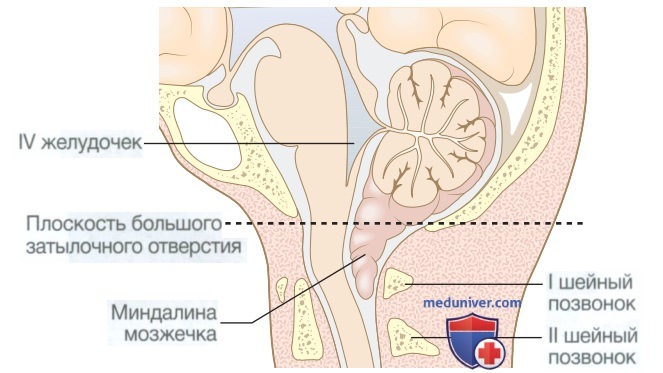

Внутричерепная гипотензия: КТ-исследования и их интерпретация

Раздел: Образы вокруг